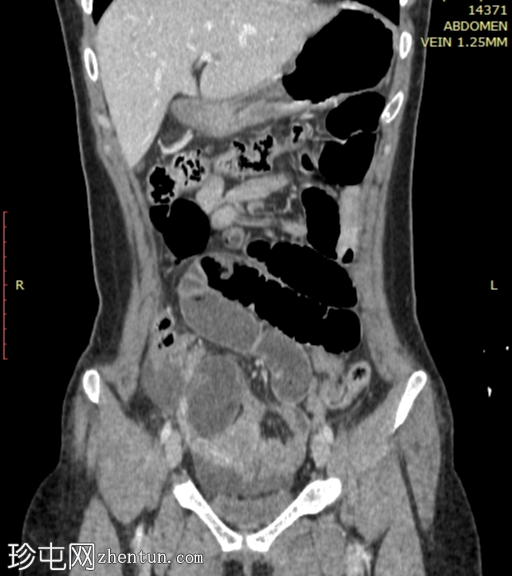

冠状位增强扫描(门静脉期)

小肠袢明显扩张,左侧附件区可见双移行点,远端回肠短段闭袢梗阻,肠颈位于左侧输卵管/左侧子宫血管附近。

肠系膜血管充血,腹盆腔可见游离液体,提示肠系膜充血。

远端回肠袢和结肠已减压。

无肠缺血或穿孔的影像学证据。

CT 检查结果提示左侧附件水平小肠短段闭袢性梗阻。肠段的移行点和形态提示可能存在阔韧带或与左侧附件结构相关的粘连带引起的内疝。